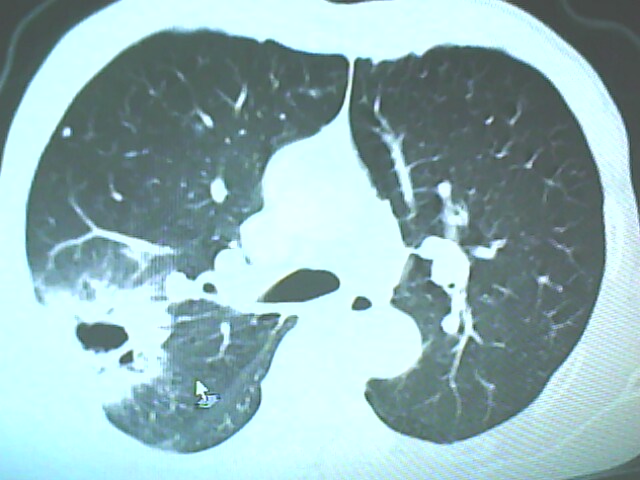

患者,男,66岁,以咳嗽、咳痰伴胸痛来就诊。

胸片提示右上肺占位病变。请各位老师看看ct。

考虑癌性空洞可能性大,空洞内壁不规则,病灶周围模糊,分叶、有毛刺

空洞内壁不规则,病灶周围模糊,分叶、毛刺呈日光放射状,突然截断,支持考虑癌性空洞

考虑右肺上叶后段周围型肺癌并癌性空洞形成。

考虑癌性空洞可能性大,内壁不规则,洞壁薄厚不均呈结节状突起,边缘模糊,分叶,毛刺

典型癌性空洞(偏心性,壁厚薄不均,内壁不光整),周围毛刺较僵硬,且有刺突征和血管聚集征